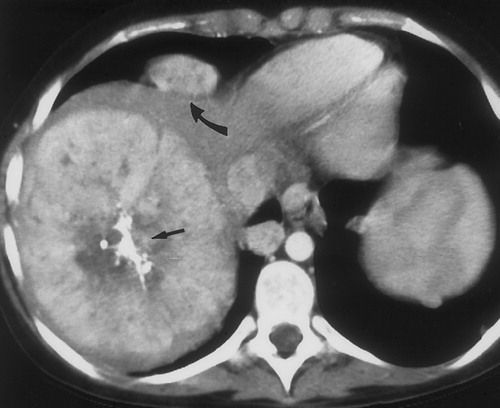

Hepatic adenoma is a benign liver tumor, most commonly seen in young women (15 to 40 years of age). Risk factors include; oral contraceptive use, female sex, and use of anabolic steroids. Patients are usually asymptomatic but may present with right upper quadrant pain. It is mostly discovered as an incidental finding on abdominal imaging studies. Its malignant potential is very low i.e. less than 1%. However, the adenoma may rupture, leading to hemoperitoneum and hemorrhage. Diagnosis is made by CT scan, ultrasound, or hepatic angiography. Treatment options include discontinuation of oral contraceptives and surgical resection of the tumors which are greater than 5 cm.